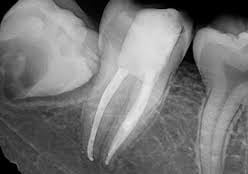

A root canal treatment is a dental procedure to remove inflamed or infected pulp on the inside of the tooth which is then carefully cleaned and disinfected, then filled and sealed. Root canal treatment is designed to eliminate bacteria from the infected root canal, prevent reinfection of the tooth and save the natural tooth.

First, the dentist removes everything that is inside the root canal. With the patient under local anesthesia, the dentist makes a small access hole on the surface of the tooth and removes the diseased and dead pulp tissue with very small files.

2. Filling the root canal

After root canal therapy, the tooth is dead. The patient will no longer feel any pain in that tooth because the nerve tissue has been removed, and the infection has been eliminated.

3. Adding Filling or a Crown

However, the tooth will be now more fragile than it was before. A tooth with no pulp must receive its nourishment from the ligament that attaches the tooth to the bone. This supply is adequate, but in time, the tooth will become more brittle, so a crown or filling offers protection..

Root canal therapy will usually save the tooth and eliminate the pain.